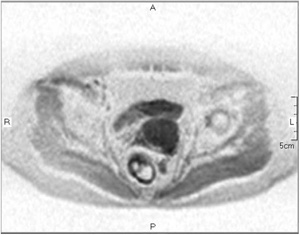

骨盤領域は脂肪組織に富むため,脂肪抑制が難しい部位の1つである。子宮病変検査へのH-sincパルスの適用例を図1に示す。本図から,安定して脂肪が抑制されていることがわかる。

図1 骨盤部画像例

a:H-sinc併用T1WI

b:T2WIc:H-sin

c:H-sinc併用DWI(b=50s/mm2)

d:H-sinc併用(b=800s/mm2)